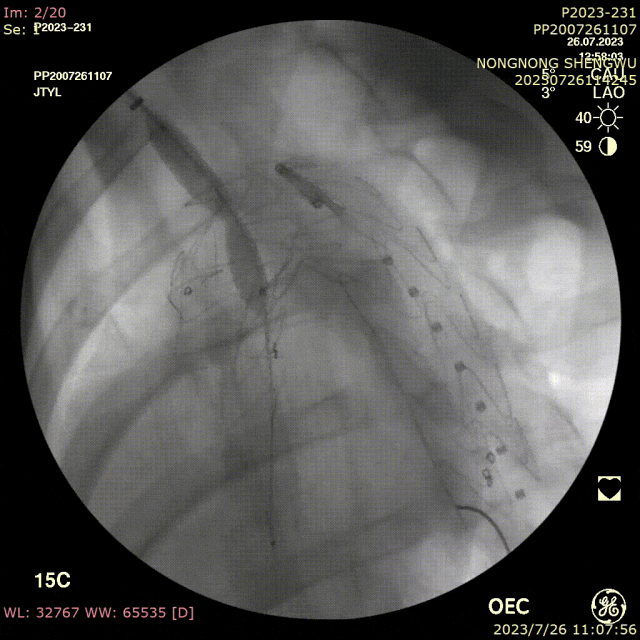

手术过程:

全麻下双上肢穿刺,右股动脉切开,左上肢路径造影,右上肢进保护性导丝,对支架预开窗后植入升主,因破口较大,支架近端掉入破口,远端扭转遮蔽左颈总动脉及头臂干,窗口对破口,再次植入一枚38-80支架,封住近端破口后,以8*60支架开放右侧头臂干,6*10人工血管行右锁骨下-左颈总搭桥,取颈前静脉行左椎动脉-人工血管搭桥,之后造影,头臂动脉均通常,术后约2小时患者清醒。